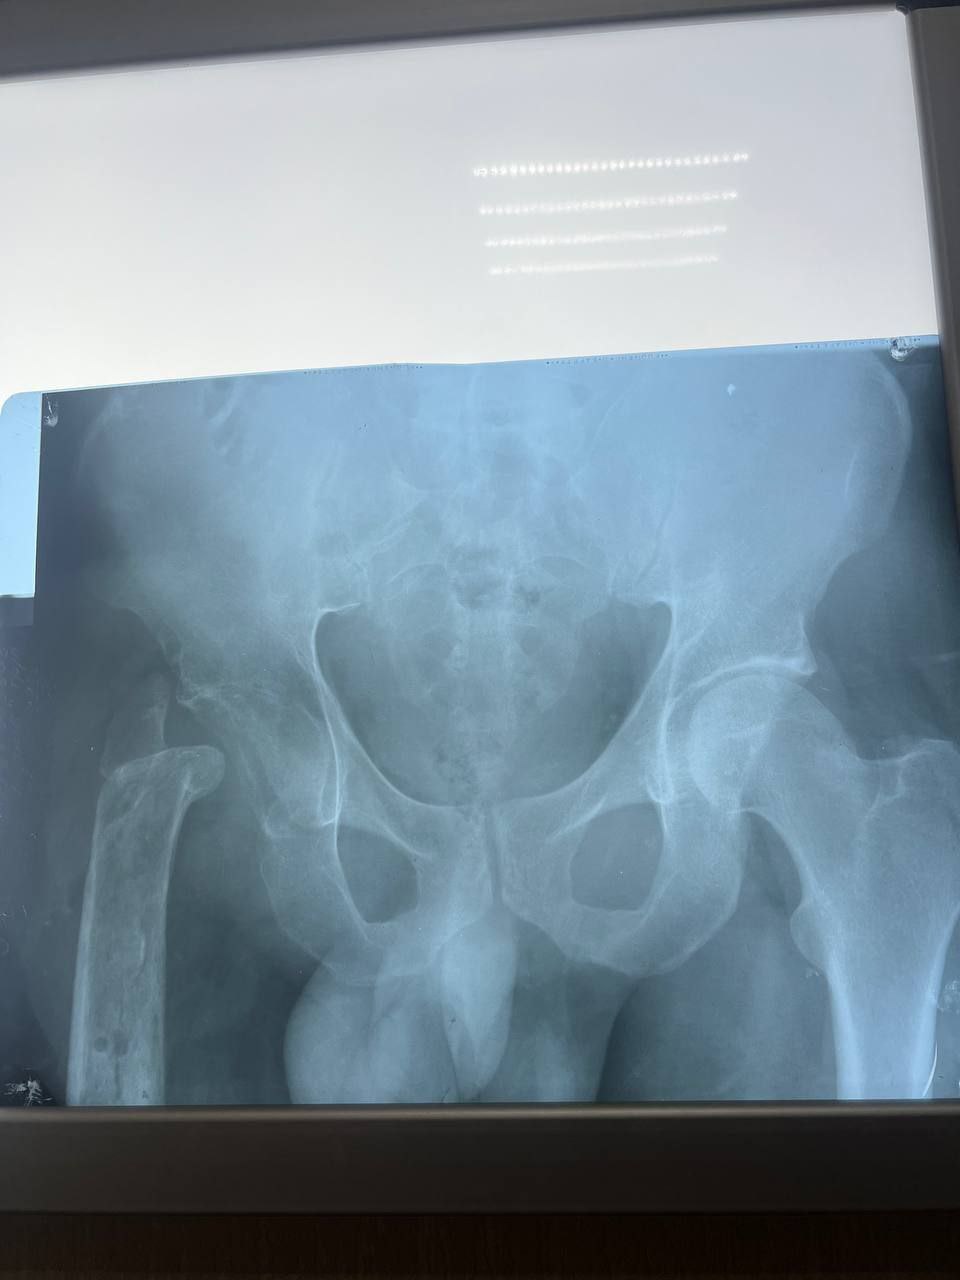

Из-за обширных повреждений и многократных операций правая нога бойца стала короче левой на 8-9 сантиметров. Обычное эндопротезирование здесь было бессильно. Требовалось чудо инженерной и хирургической мысли.

Вместо стандартной замены сустава пациенту выполнили сложнейшее вмешательство с использованием ревизионных систем эндопротезирования, в ЛНР такую операцию провели впервые. Главная задача хирургов заключалась не просто в установке импланта, а в восстановлении биологической оси конечности и компенсации укорочения.

Хирургам пришлось работать в рубцово-измененных тканях после десятка предыдущих операций, убрать очаги инфекции (некроэктомия) и с помощью специальных ревизионных компонентов буквально «собрать» сустав заново, вернув ноге физиологическую длину. Для пациента это означает шанс не просто избавиться от боли, но и забыть о хромоте, вернуться к нормальной походке.

05.03.2026 — Эндопротезирование тазобедренного сустава ревизионными системами с восстановлением оси и длины конечности.